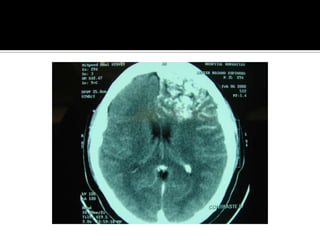

Hemorragia cerebral IntraparenquimatosaCefaleaAlteracion de la concienciaVomitoCrisis epilepticasDiagnostico: TAC de craneo simple

Hemorragia cerebral IntraparenquimatosaSitio : putaminal, nucleo caudado , talamo,lobar, cerebelosa y  puente.Etiologia : HTA,malformacion AV, angioma cavernoso y angiopatiaamiloide, drogas ( cocaina,heroína, fenilpropanolamina) anticoagulantes , tromboliticosMas de la mitad de pacientes, muere o queda con secuelas severas

Hemorragia cerebral IntraparenquimatosaCefaleaAlteracionde la concienciaVomitoCrisis epilepticasDiagnostico: TAC de craneo simple

Hemorragia cerebral IntraparenquimatosaSitio: putaminal, nucleo caudado , talamo,lobar, cerebelosa y puente.Etiologia : HTA,malformacion AV, angioma cavernoso y angiopatiaamiloide, drogas ( cocaina,heroína, fenilpropanolamina) anticoagulantes , tromboliticosMas de la mitad de pacientes, muere o queda con secuelas severas

Tratamiento EVC HemorragicoMediciondel hematoma y sobrevida:la mayor morbimortalidad ocurre al medir mas de 30 ccCon un volumen de 60 cc y EGC de menos de 8, tienen una mortalidad del 91 %.Con volumen del 30 cc y EGC mayor de 9, la mortalidad fue del 19 %.

Hemorragia cerebral intraparenquimatosaMediciondel hematoma: ABC/2Crecimiento del hematoma: al menos38 % de pacientes tiene un crecimiento del 33% en las primeras 24 hrs.No se requiere angiografia cerebral